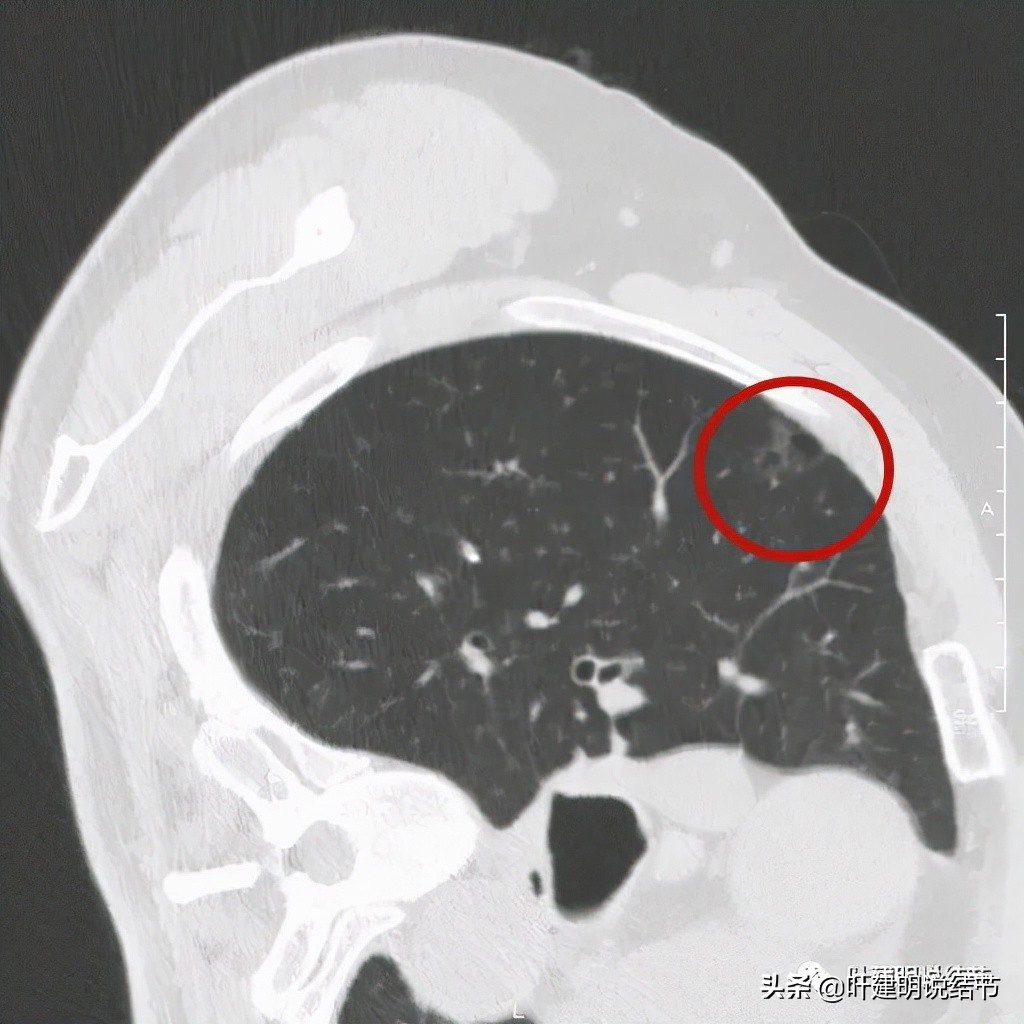

以上诸图是病灶4:考虑囊腔型肺癌可能性大,壁厚薄不均,内壁不光滑,有血管进入病灶,有少许密度偏高的成分,但纵隔窗上未见,不是真正意义上的实性成分。